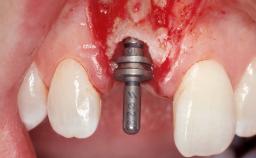

Late Flapless Placement of an Implant in a Maxillary Left Central Incisor Site

A 39-year-old male patient presented with a chief complaint of discomfort and gingival discoloration around his maxillary left central incisor. He was in good general health and was a non-smoker. His past dental history was significant because of the traumatic fracture of tooth 21 in a sporting accident at age 13. Initial dental treatment included endodontic therapy and a full-coverage restoration. The patient became symptomatic 5 years later, when structural failure of the tooth resulted in the dislodgment of the crown. Endodontic retreatment, apical surgery, and post-and-core restoration were performed.